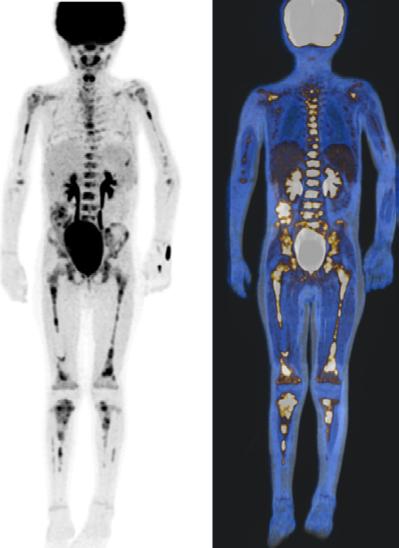

Los tejidos malignos mayormente desdiferenciados son ávidos por 2-[ 18 F]FDG debido a una mayor tasa de metabolismo de la glucosa (Figura 2). El PET con 2-[ 18 F]FDG se utiliza cada vez más en neoplasias malignas pediátricas, incluido el neuroblastoma. Varios estudios han confirmado que la mayoría de las lesiones de neuroblastoma concentran 2-[18F]FDG, el cual se acumula en el neuroblastoma no ávido de mIBG. El 2- [18F]FDG se recomienda como reempla-

Figura 2A) Estudio PET con 2[18F]-FDG, positivo para captación del radiofármaco en esqueleto axial y apendicular en un paciente con diagnóstico de Neuroblastoma de 9 años.

Figura 2B) Estudio PET/RM con 2[18F]-FDG donde se identifican las lesiones funcionales con corregistro anatómico en esqueleto axial y apendicular. Estas imágenes denotan un neuroblastoma de estirpe probablemente desdiferenciada y de pobre pronóstico.